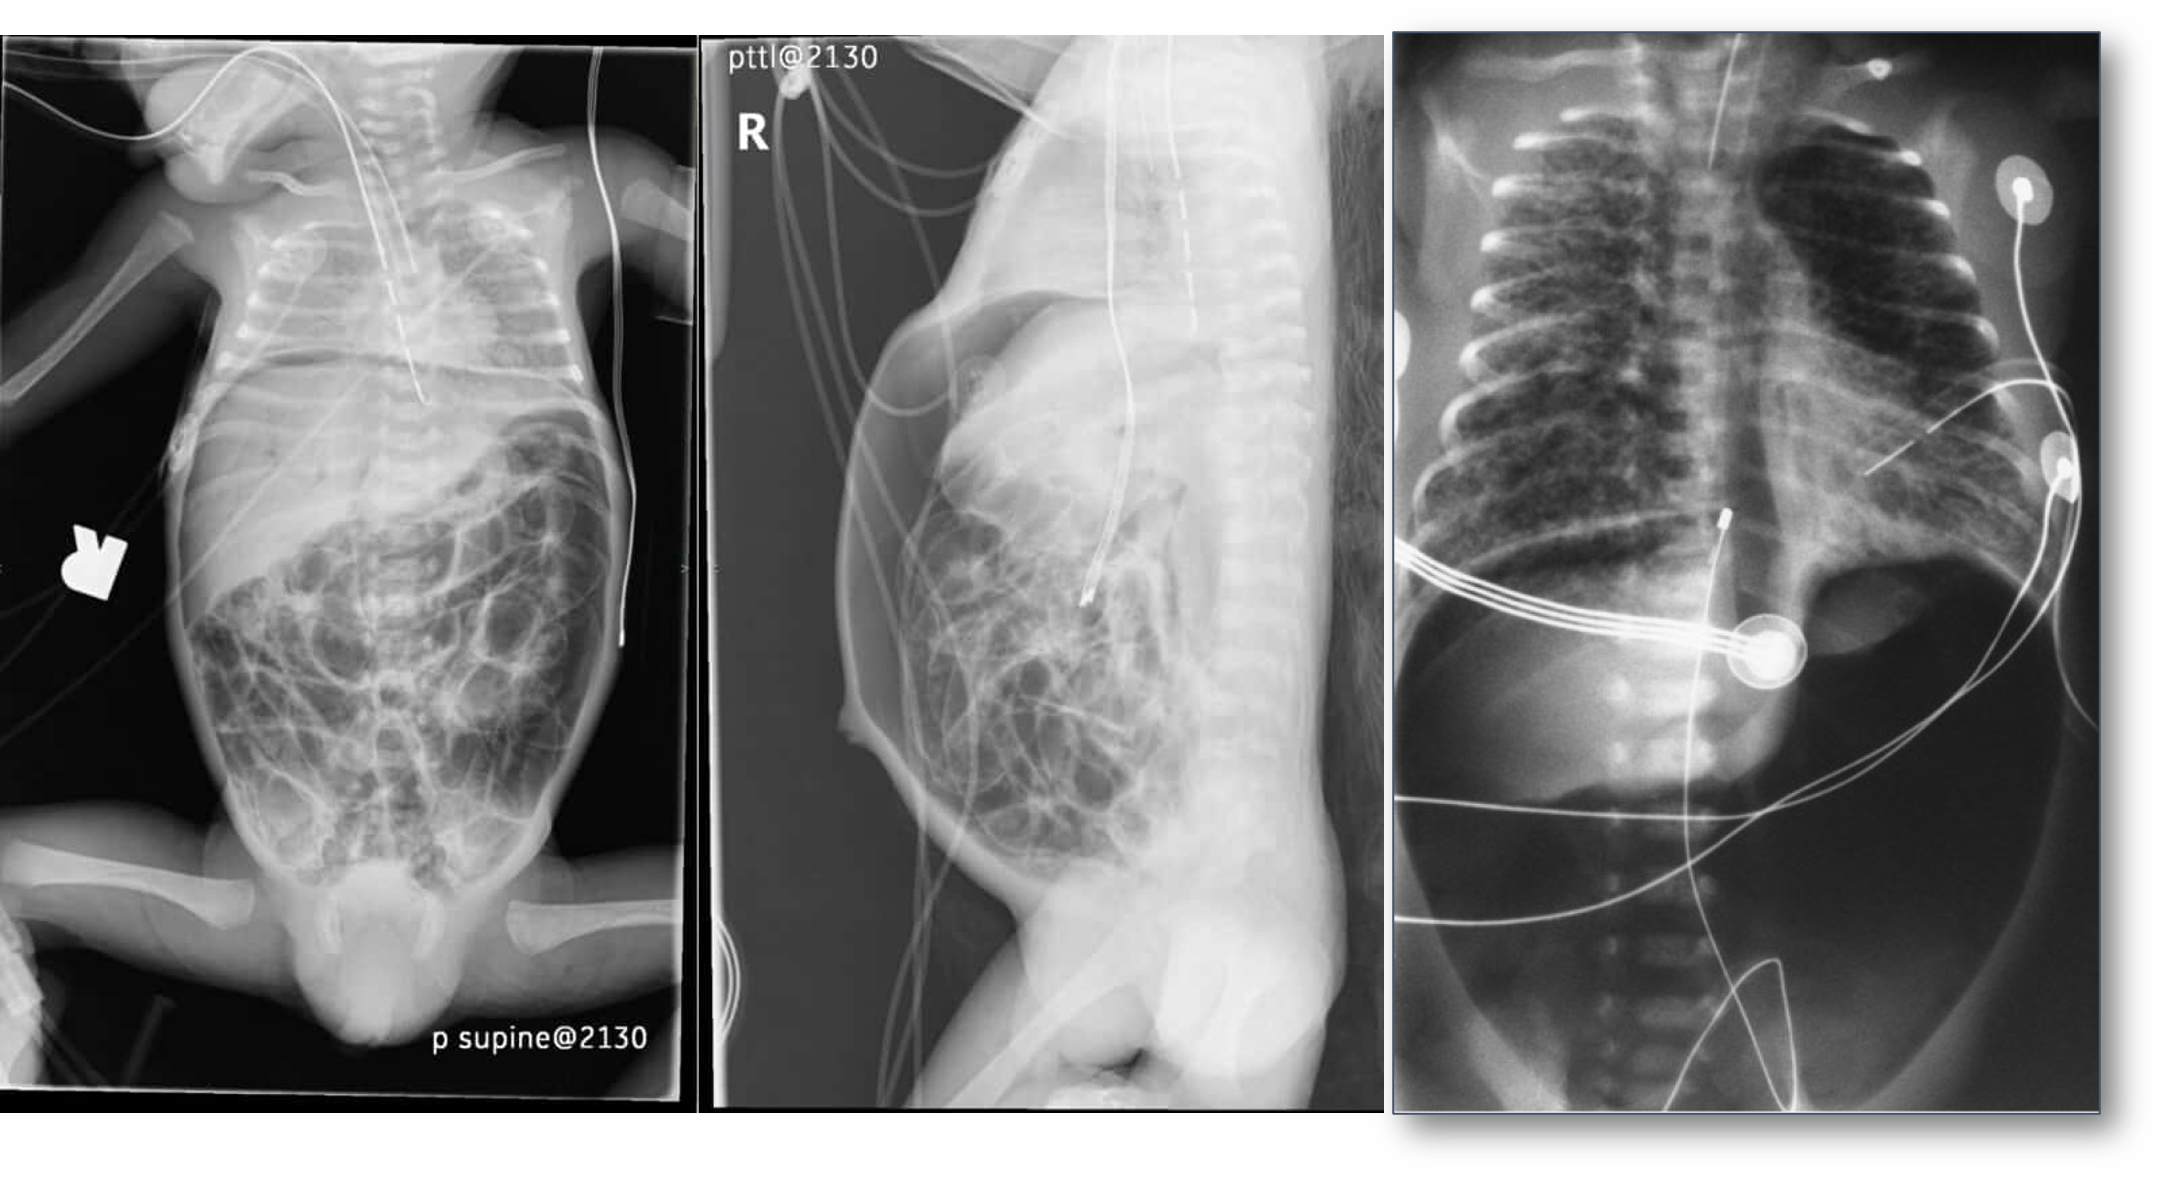

- Dilated loops,

- thickened bowel walls,

- pneumatosis intestinalis (air in intestinal walls),

- pneumoperitoneum; indicate perforation (emergency requiring surgical intervention),

- portal gas (present in the portal venous system,

- considered to be a poor prognostic sign).

inflamed, necrosis ⇒ Perforation everywhere

dark circles air in intestinal wall

Air in portal gas

Pneumoperitoneum

- Notice:

Pneumoperitoneum. - due perforations